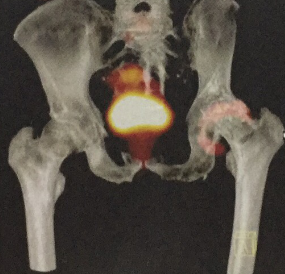

PET/CT(图2-9)是将PET和CT两个成像技术结合起米的融合成像设备,实现了PET和CT图像的同机融合(图2-10)。使PET的功能影像和螺旋CT解剖影像两种显像技术的优点融于一体,形成优势互补,一次成像即可获得PET图像,又能获得相应部位的CT图像,对病灶进行准确定位和定性,为医生提供更多的诊断信息。CT、PET以及 PET/CT成像的对比见图2-11。

图2-9 PET/CT设备